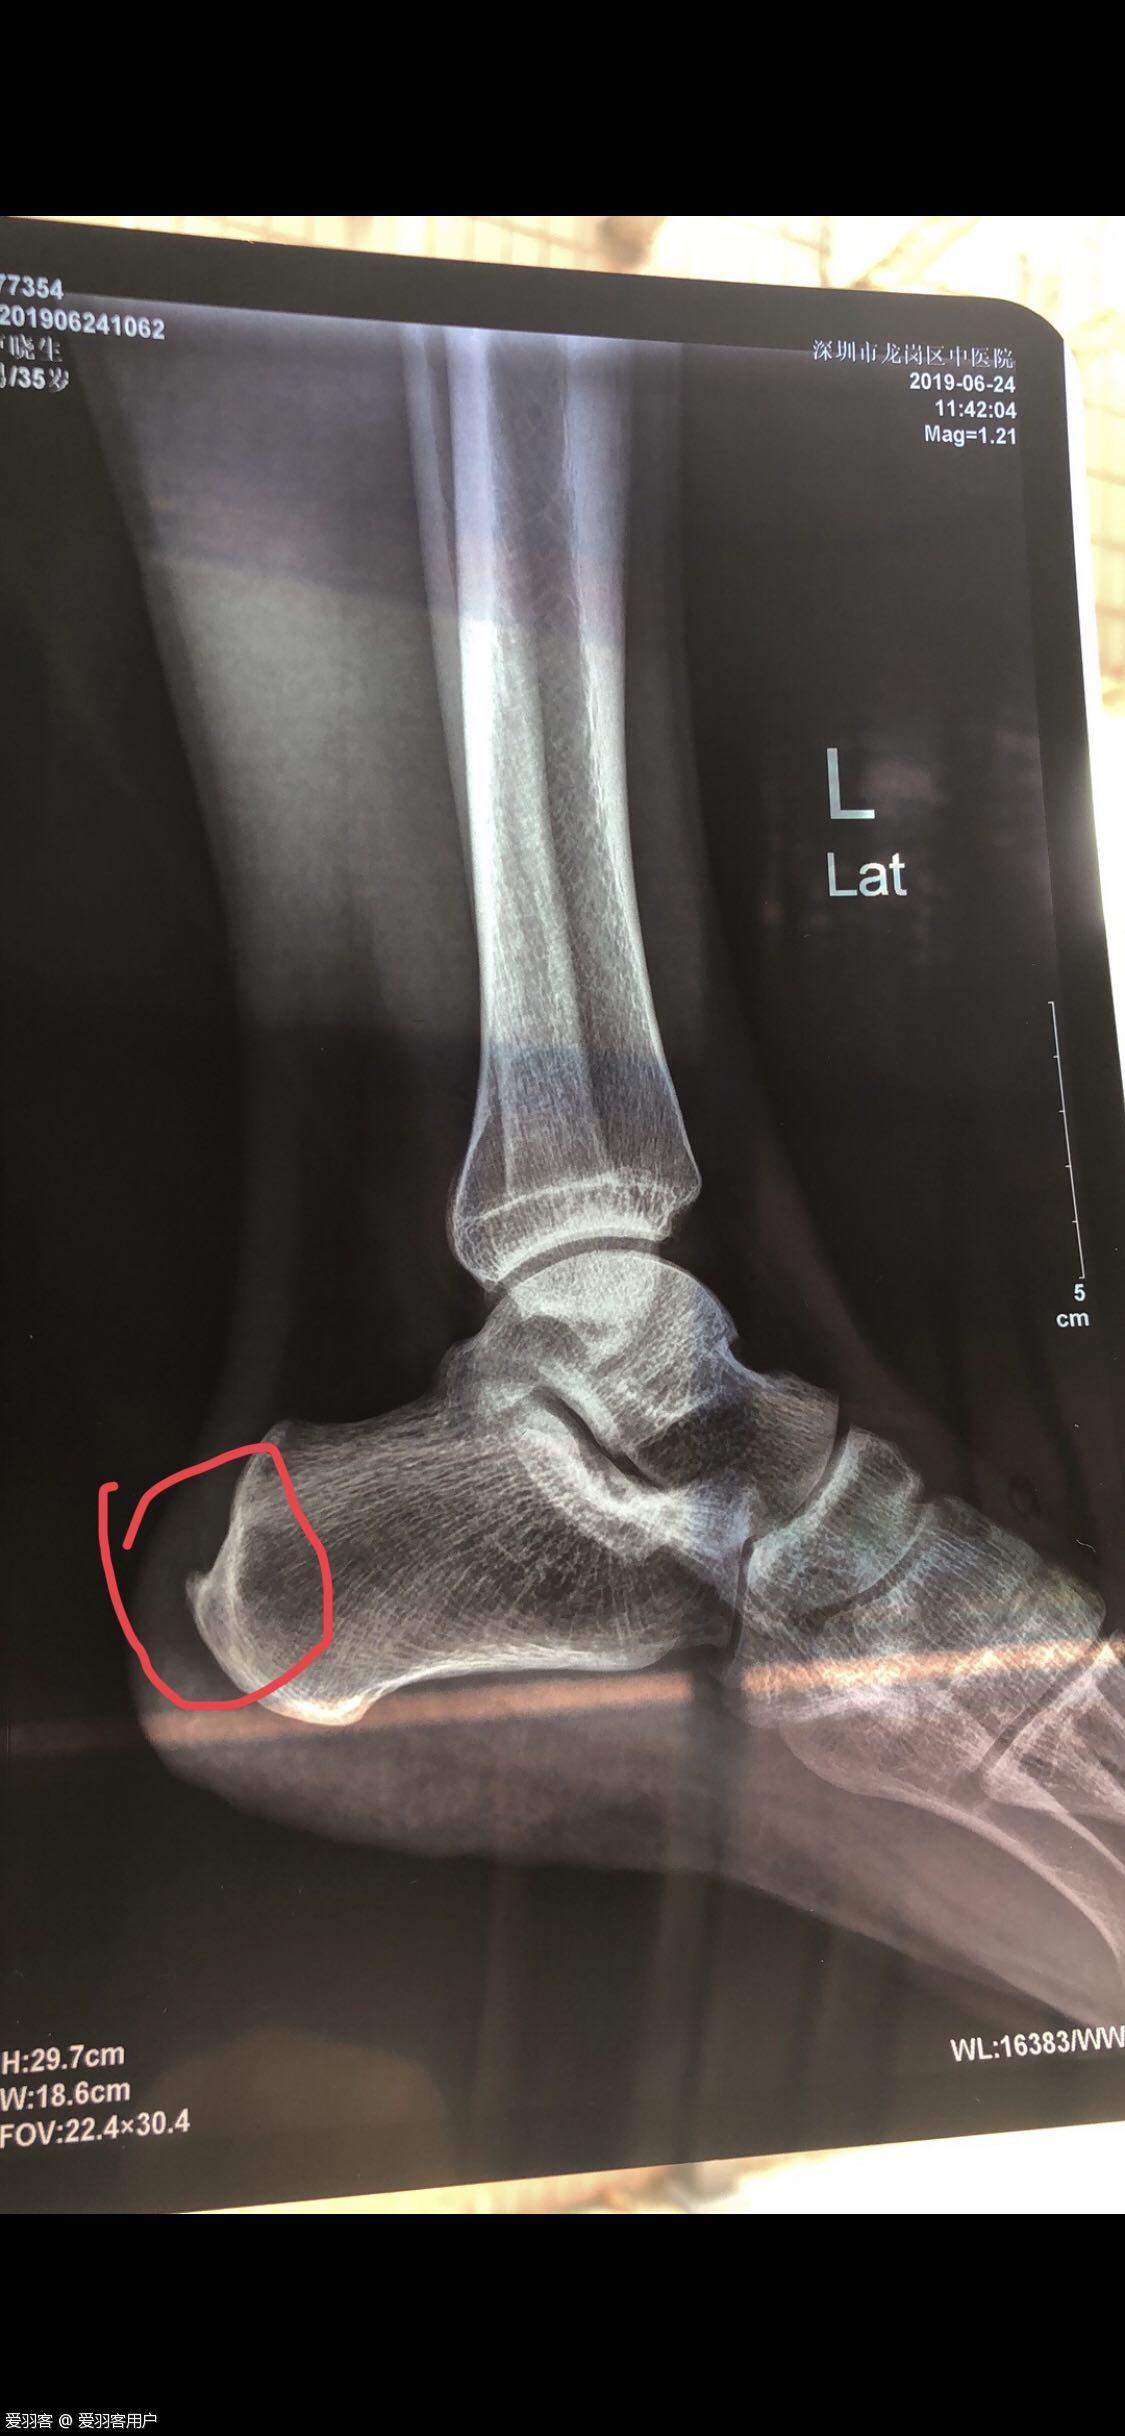

跟骨长骨刺,已经四个月了,医生说以后不能强烈运动,这不是宣判我死刑了吗?有没有同病的球友,你们好了吗?